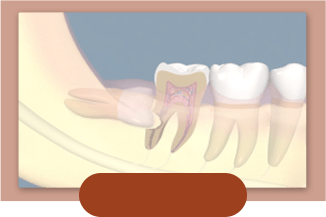

阻生智齿

-

发炎的智齿

-

智齿蛀牙

-

侵犯邻牙

-

无对咬牙

-

萌出时肿胀疼痛